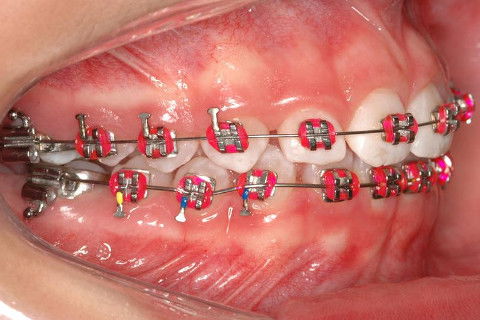

INSTALAÇÃO APARELHO FIXO SUPERIOR E INFERIRO (ROTH)

CLASSE I

CLASSE II